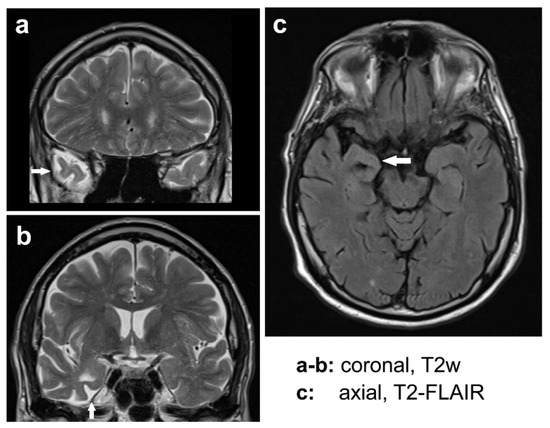

3.5. Neurology